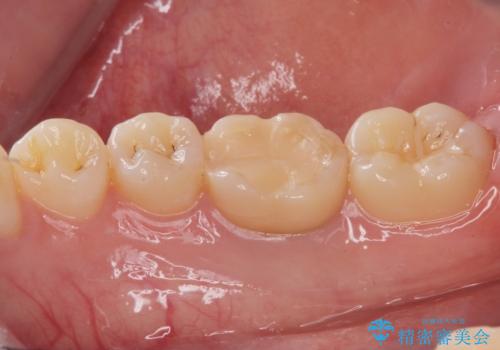

- 右下6 仮歯+ジルコニアクラウン 11,000円+110,000円費用は治療当時の料金となります

インレーにすると残った歯が薄くなってしまう場合は術後の破折リスクが高いためクラウンで修復することがあります。